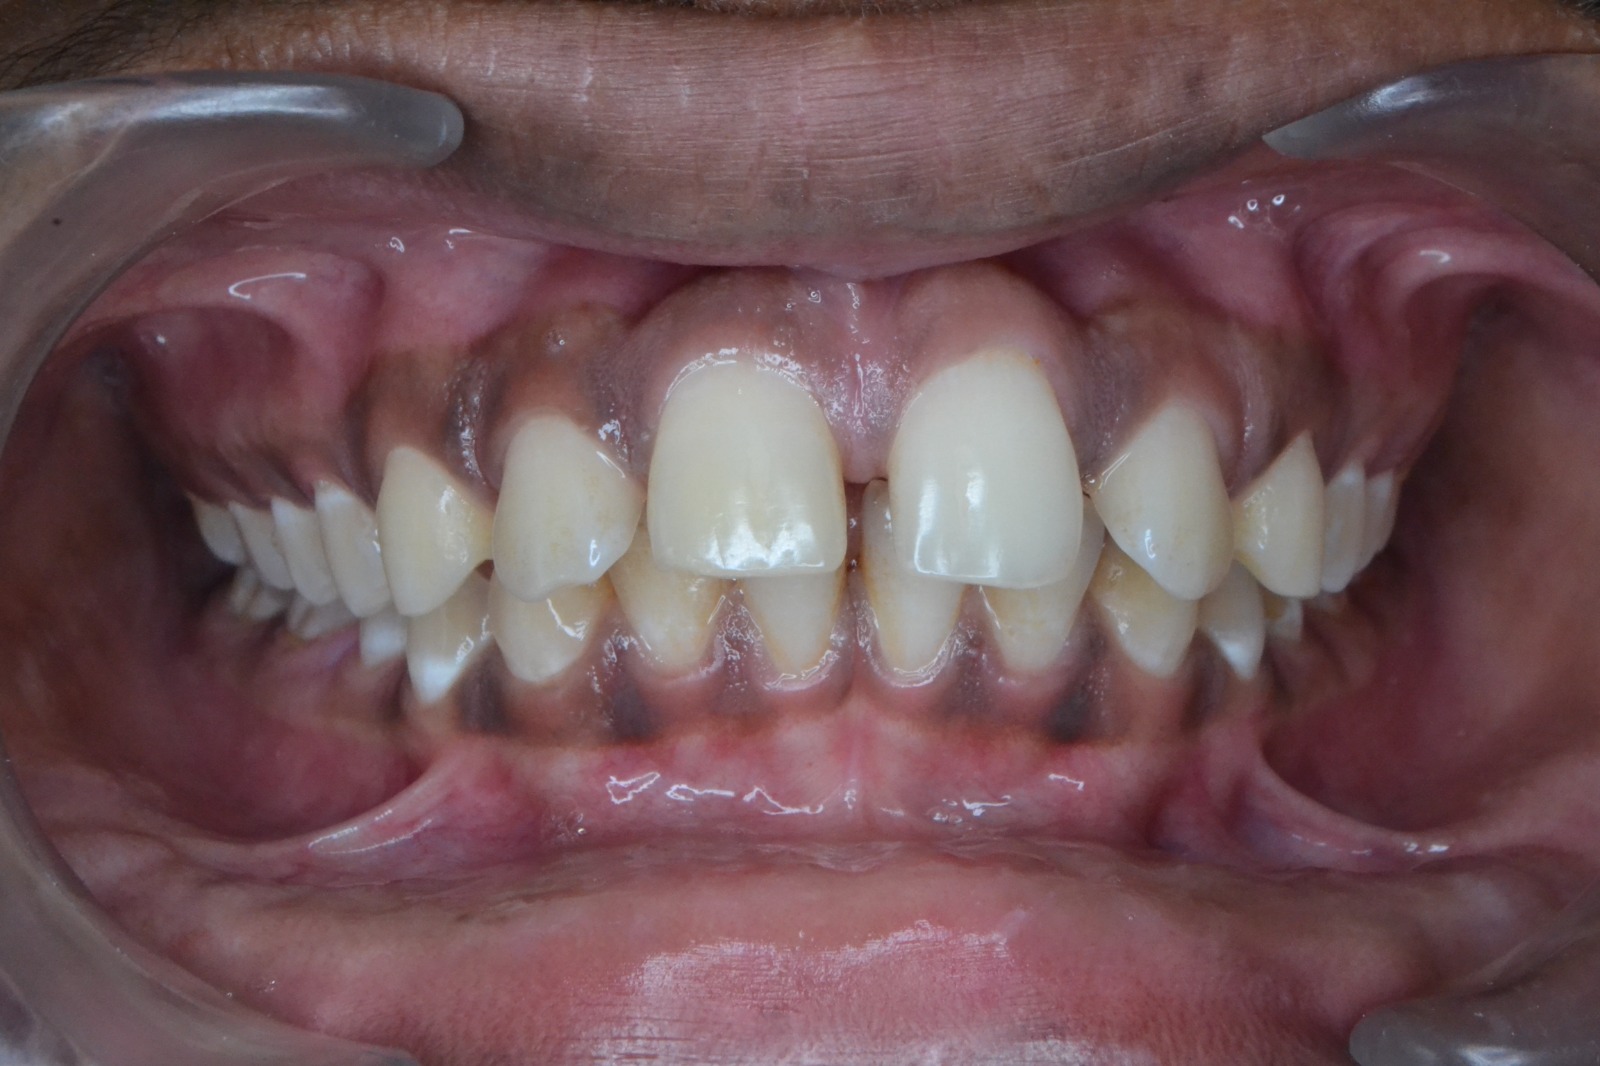

After/Before

See stunning smile transformation before and after

Before After